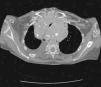

Chylothorax linked to goiter solved by transcervical total thyroidectomy without sternotomy

Quilotorax provocado por un bocio resuelto mediante tiroidectomía total con abordaje cervical sin esternotomía